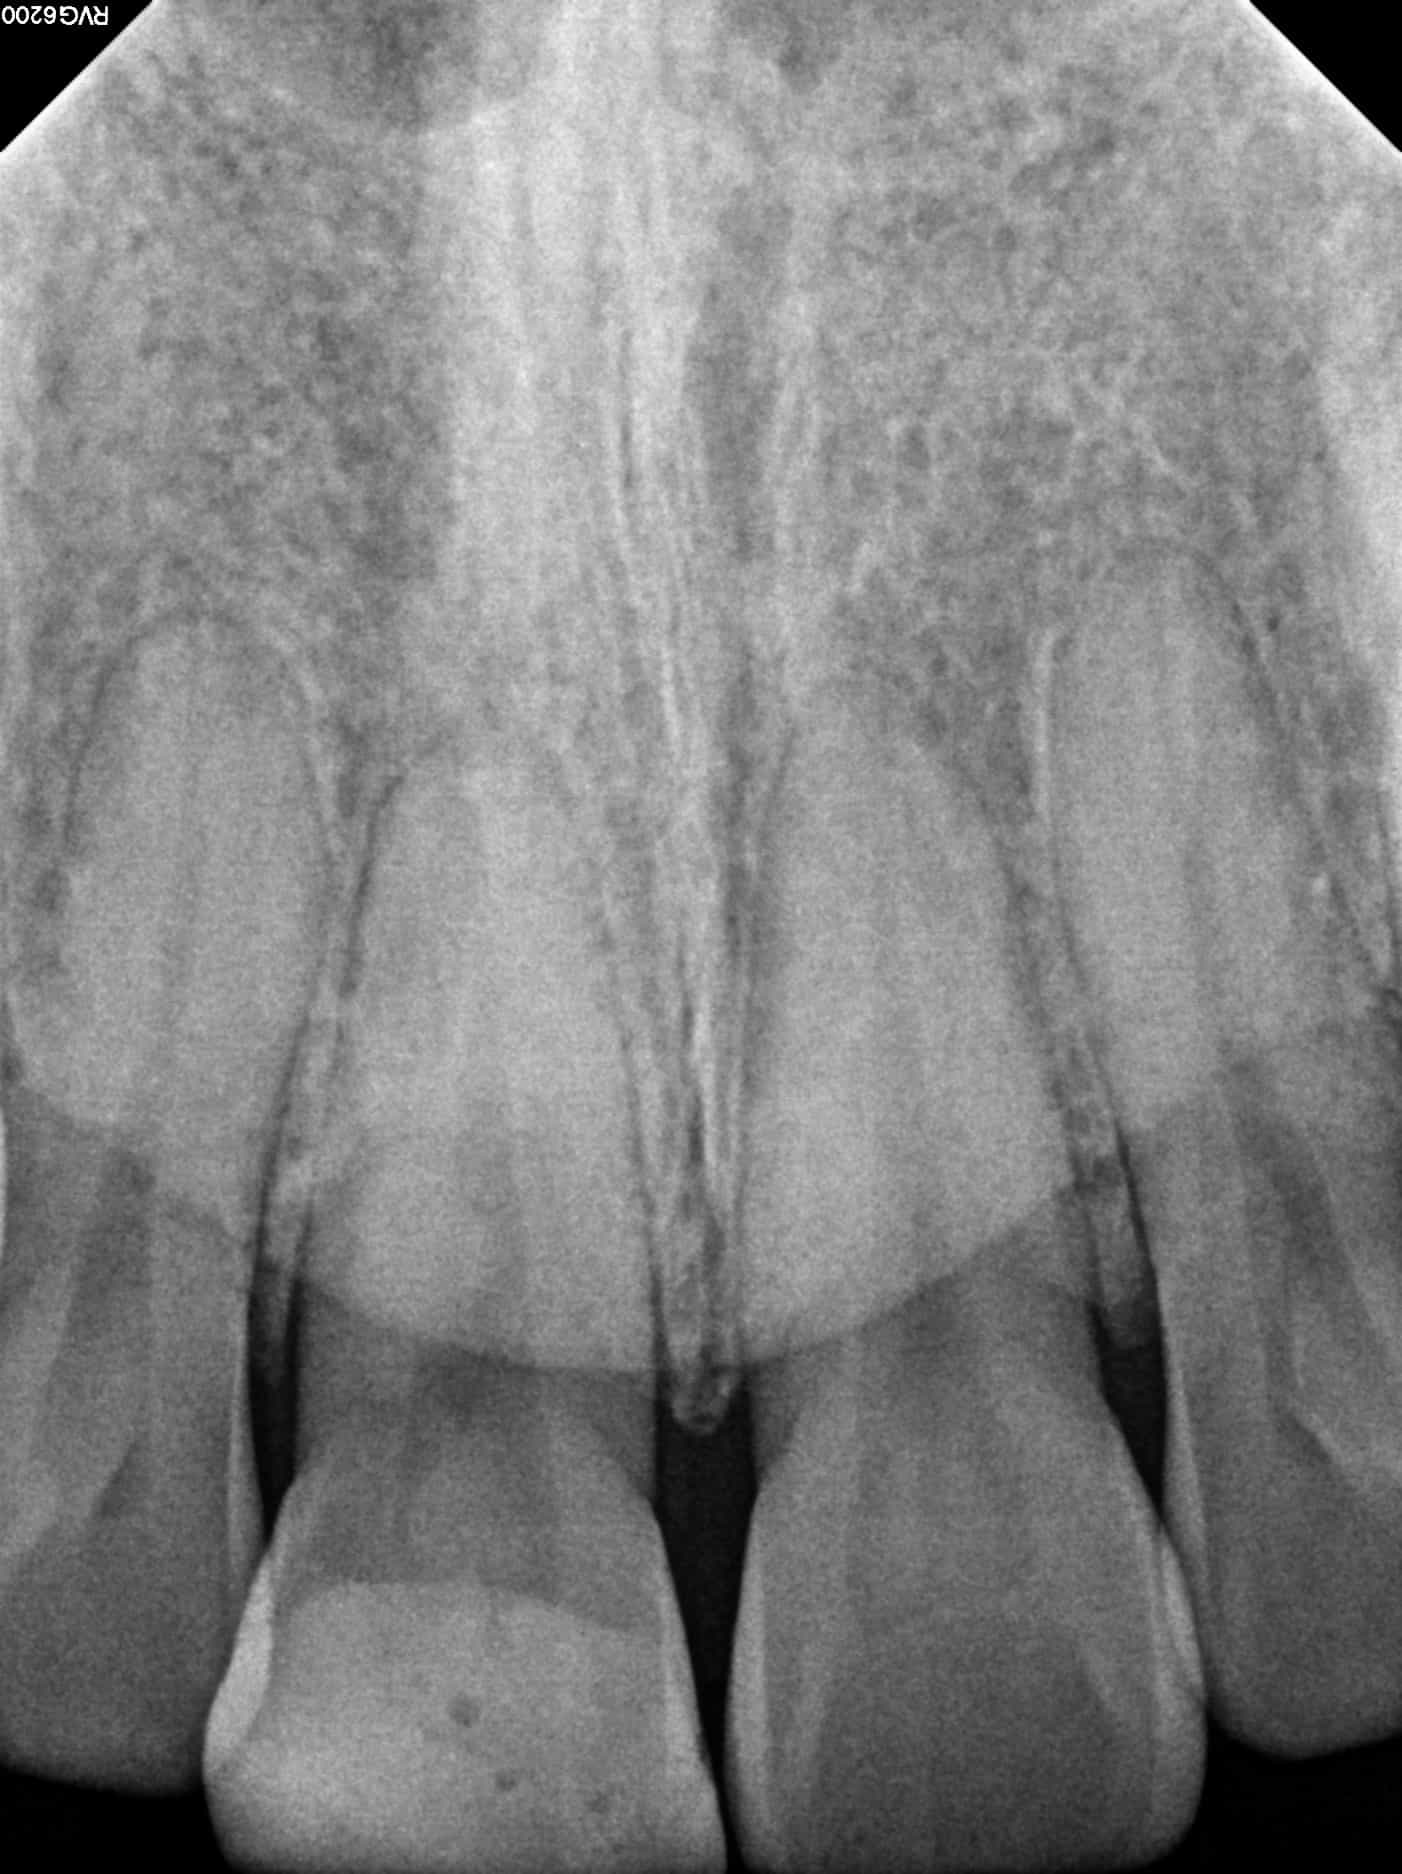

We first took a periapical radiograph, and there was no evidence of either periapical pathology or fracture. Pulp testing revealed normal responses from all the upper anterior teeth. In addition, no tenderness to either palpation or percussion was elicited. In other words, everything appeared normal both clinically and radiographically.

Lastly, I decided to take a CBCT to rule out any abnormality. To my surprise, a portion of the tooth had fractured off and become dislodged lingual to the tooth. Fortunately, the segment was removed easily and the patient’s symptoms resolved immediately.